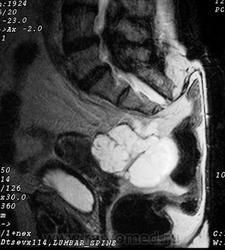

Сакральная хордома. Д-р Марсело Сенна Ксавье де Лима, Paul Roland Kaleff, и Антонио Рожерио del'Arco Roth Аугусто Варгас. Рецидив. Часть крестца была удалена ранее. Пнд, 27/11/2017 - 21:03 #1 Катенёв Валенти... Не на сайте Был на сайте: 7 лет 4 месяцев назад Зарегистрирован: 22.03.2008 - 22:15 Публикации: 54876 Внутричерепная хордома. http://pubs.rsna.org/doi/full/10.1148/rg.234025176 Пнд, 09/07/2018 - 20:44 #2 Катенёв Валенти... Не на сайте Был на сайте: 7 лет 4 месяцев назад Зарегистрирован: 22.03.2008 - 22:15 Публикации: 54876 Продолжение. Приложения: